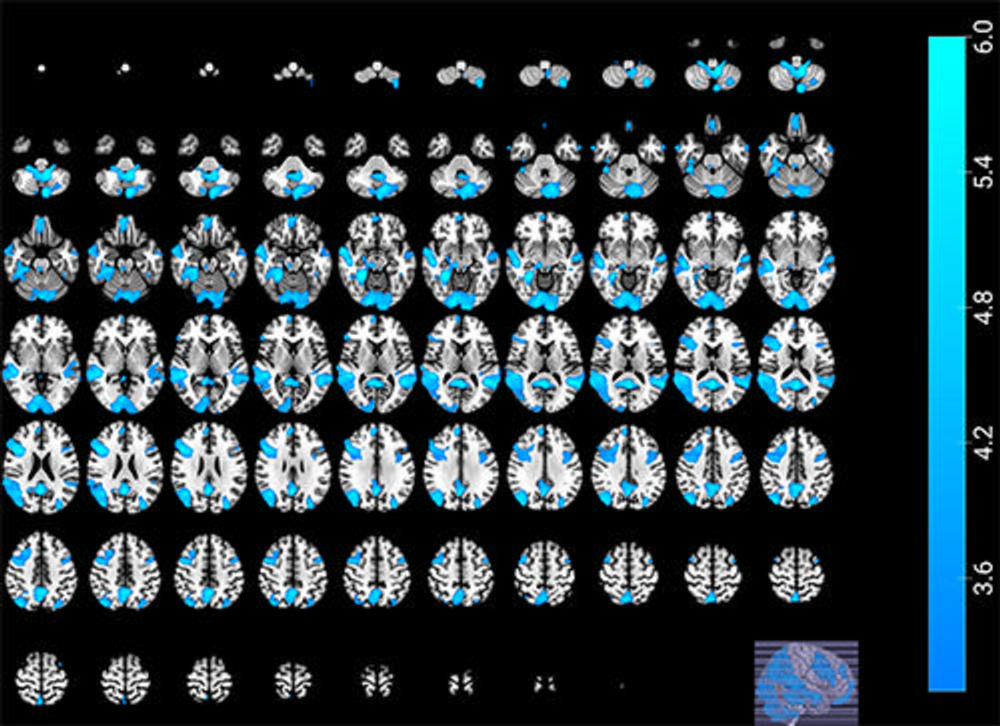

Figure 2. Significant defeat contrast shows the brain activity of soccer fans resulting from the subtraction of fans’ brain activations when their team is defeated by the archrival team, minus when their team is defeated by other teams (Rival -> Fan > Other -> Fan).

High-res (TIF) version